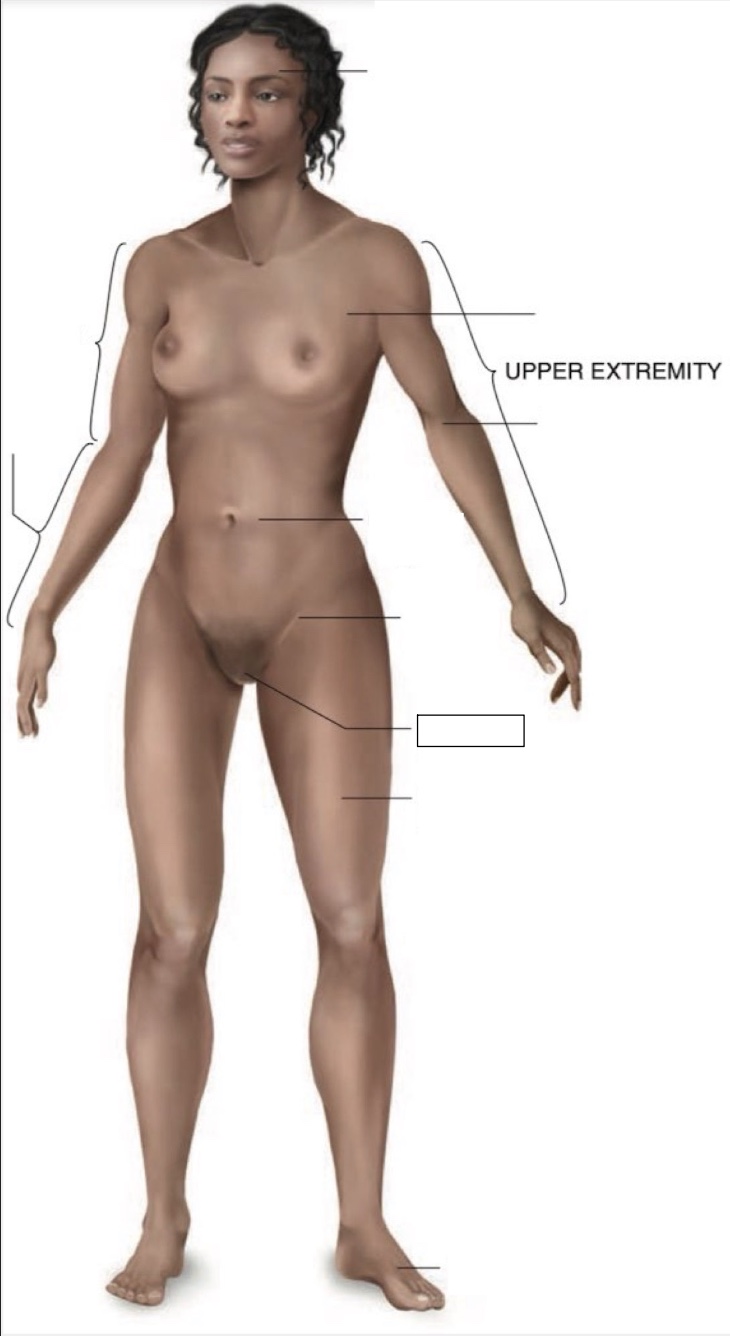

genital region